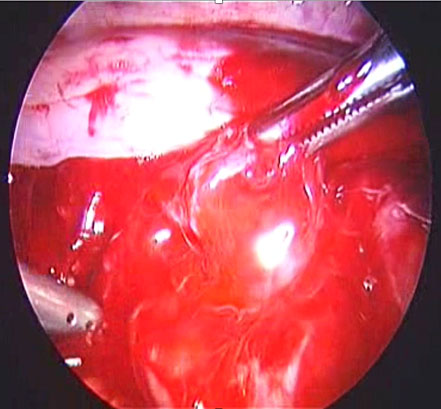

In the event of uterine artery bleeding during dissection, once identified, the laparoscopist should remain calm. CO₂ insufflation and suction at pressures below 300 mmHg help maintain pneumoperitoneum. The bleeding vessel should be carefully grasped with bipolar cautery forceps or another appropriate instrument (Figure 17) after adequate dissection. Occasionally, the presence of a gauze piece can help localize the bleeding source. It is important to avoid forcefully grasping the bleeding area, as the uterine artery lies above the ureter, which in turn is above the uterine vein. If the bleeding originates from the vein, bipolar cautery may inadvertently damage the ureter. Once hemostasis is achieved, hemostatic agents such as Surgicel may be applied, although they are often unnecessary.

(a) |

(b) |

(c) |

17

(a) Right uterine artery active bleeding after removal of the uterus. (b) Stabilizing the bleeder by atraumatic forceps with suction. (c) Stabilized tip of the vessel coagulated with bipolar cautery forceps.